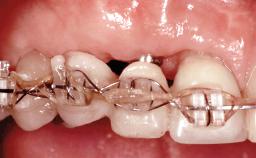

Replacement of Four Incisors with a Fixed Partial Denture on Two Narrow-Neck Implants after Implant Failure

| Mesio-Distal Space | Adequate for the replacement of all missing teeth |

| Occlusion/Articulation | Harmonious |